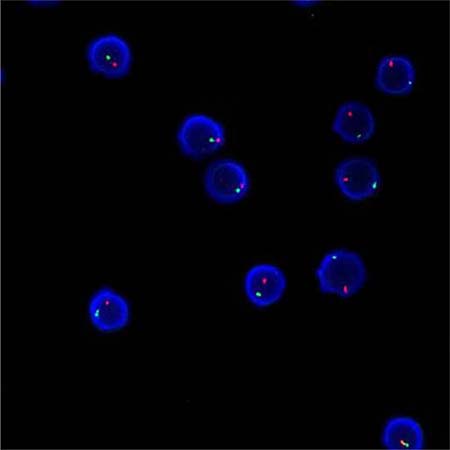

Method of chimerism testing

Applying the STR technology, polymerase chain reaction(PCR) carries out multiplex amplification of 16 gene loca (namely 15 STR loca and 1 amelogenin locus) and tests by three-color fluorescence (see Figure 8). The design focused on amplimers of these loca and DNA amplification of the same scale was conducted by PCR. Different numbers of replications of repetitive sequences within the amplified region led to typing differences of allele. After electrophoretic separation, different genotypes can be distinguished by fluorescence detection. Before transplantation, peripheral blood or bone marrow of donors and recipients were sampled respectively to identify their STR loca. According to STR loca maps of donors and recipients before transplantation, proportions of cells from donors and recipients, namely donor cell chimerism, can be obtained by calculation (see Figure 9). Fluorescently-labeledDNA probes were used for fluorescence in situ hybridization (FISH). By the complementarity between probes and DNA base pairs of samples, after hybridization of probes and DNA of samples, outcomes were obtained to examine chromosomal or genetic abnormality in cells and tissue samples in accordance with fluorescence signals detected with fluorescence microscope. The name of probe used in this study: CEPX SpectrumOrange/Y SpectrumGreen DNA Probe Kit(Model: 7J20–50), probe map (see Figure 10). According to ISCN2013, CEPX/Y was named nuc ish (CEPX) × 2 [495/500], indicating that gene CEPX of 495 out of 500 interphase nuclei had two copies (see Figure 11). CEPX/Y was named nuc ish (CEPX, CEPY) [495/500], showing that 495 out of 500 interphase nuclei had one copy of CEPX and CEPY (see Figure 12).